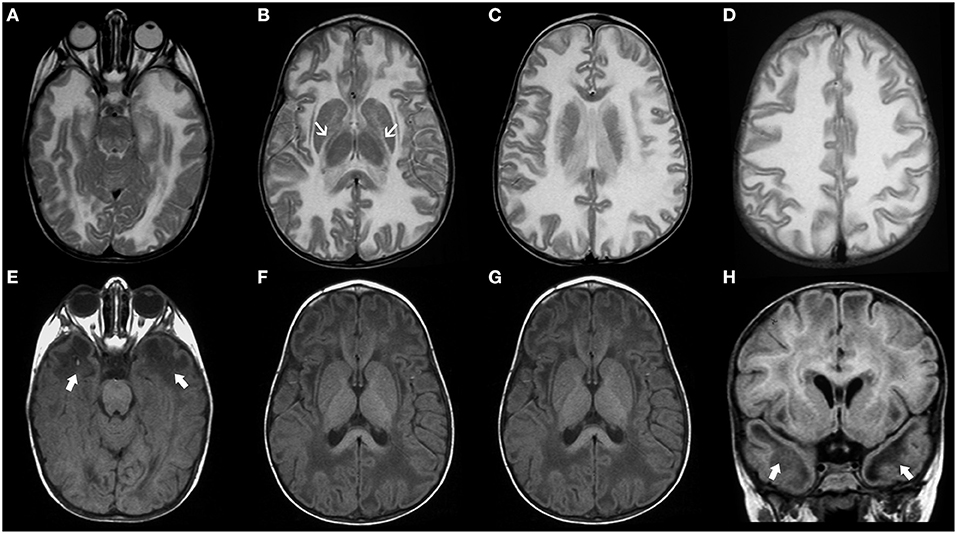

Vanishing white matter disease, especially the classic early-infantile form, is usually a well-recognizable disorder, characterized by diffuse and symmetric T2WI/FLAIR hyperintensities involving mainly the deep and sub-cortical white matter with progressive rarefaction and cystic degeneration, with corresponding increased diffusion and eventually a parenchymal CSF-like signal (Figure 8). Radiating stripes may be detected inside the cystic areas on T1WI, FLAIR, and PD. The cerebellar white matter and the central tegmental tracts may also be involved, while the outer rim of the corpus callosum, the anterior branch of the internal capsule, and the anterior commissure are usually spared. Proton spectroscopy reveals progressive disappearance of the major metabolites, replaced by lactate and glucose (92, 95, 96).

Figure 8. Imaging characteristics of Childhood Ataxia with Central Hypomyelination/Vanishing White Matter Disease (CACH/VWMD). Axial T2WI (A–D) and FLAIR (E–H) of an 11-year-old boy with CACH/VWMD demonstrates bilateral, confluent, symmetric periventricular, and deep white matter hyperintensity, with relative sparing of the anterior limb of the internal capsule (black arrowheads) and the subcortical white-matter/U-fibers. There are areas of cystic degeneration around the frontal horns (white arrows) and in the centrum semi-oval bilaterally (thick black arrows), with some radiation stripes depicted within the latter location.